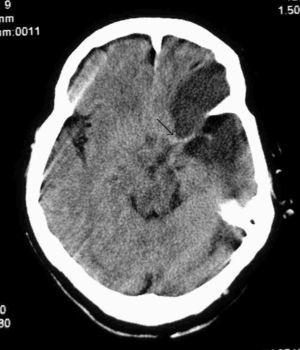

Paciente de 73 años con antecedentes de hipertensión arterial (HTA), diabetes no insulino-dependiente, hipotiroidismo, hipercolesterolemia y bronquitis crónica. Fue trasladada a nuestro hospital por el servicio de emergencias extrahospitalaria por un cuadro brusco de insuficiencia respiratoria y disminución del nivel de conciencia con hemiparesia derecha. A su ingreso en el hospital está intubada con Glasgow Coma Score (GCS) 6, presión arterial (PA): 240/100 mmHg, anisocoria con midriasis izquierda, hemiplejía derecha y Babinsky derecho. Se realiza tomografía axial computarizada (TAC) cerebral (fig. 1) que aprecia hiperdensidad de la arteria cerebral media derecha como signo precoz de lesión isquémica que todavía no se visualiza. Al ingreso en nuestra unidad se la mantiene sedada, en ventilación mecánica, controlando la PA y con tratamiento antiagregante. A las 48 horas se repite la TAC (fig. 2), observándose trombosis de la arteria cerebral media izquierda e hipodensidad frontotemporoparietal izquierda. Se mantiene consciente, afásica y hemipléjica pudiendo ser extubada y trasladada a planta. Posteriormente fallece por las secuelas de su enfermedad. El diagnóstico fue accidente cerebrovascular agudo (ACVA) isquémico y trombosis de la arteria cerebral media izquierda.

Figura 2